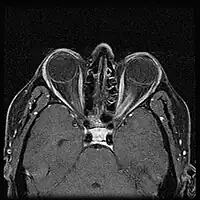

When ONSM is suspected, MRI of the brain or orbits should be performed. This will usually show characteristic findings and confirm the diagnosis.[5]